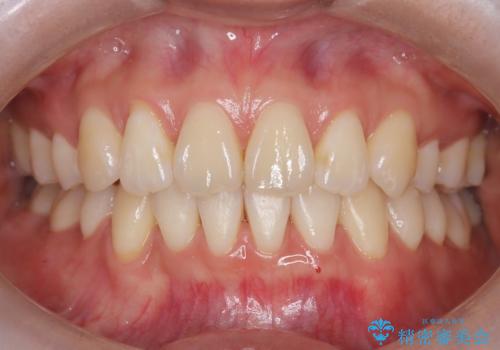

ハーフリンガル矯正による前歯部の叢生改善と口元の後退|上顎左右4番・下顎1番抜歯症例